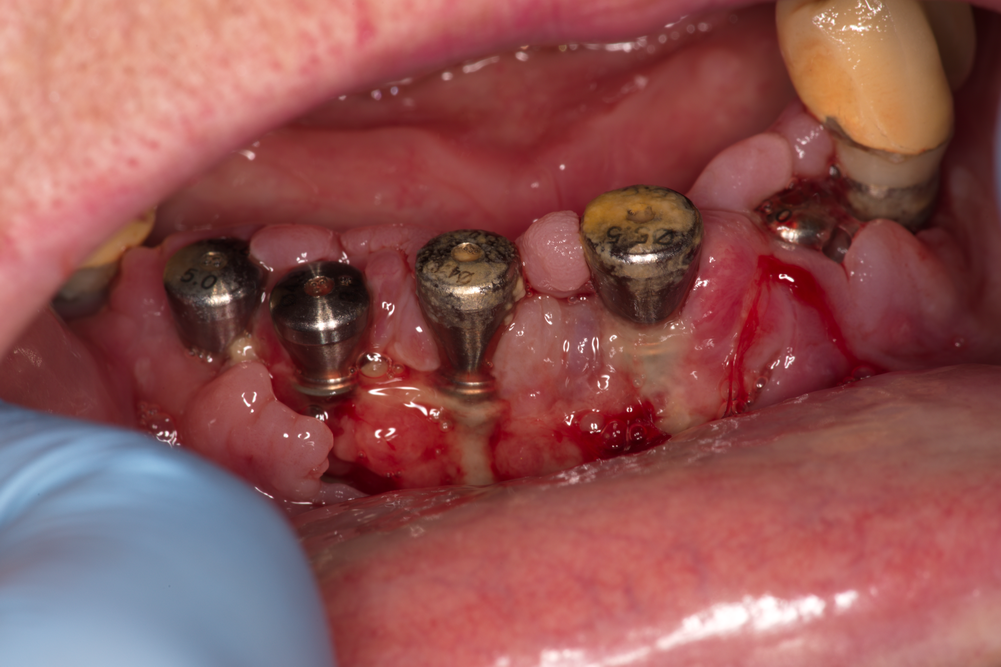

Поставянето на зъбни импланти с помощт на хирургичен водач осигурява една

успоредност на имплантатните надстройки - както е показано на горната снимка.

Подобен хирургичен протокол има много голямо предимство - улеснява в много

голяма степен протезирането върху имплантите. Още по-важното е че успоредността

в същото време прави възможно поставянето на временна или дори постоянна

протезна конструкция върху имплантатните платформи - още в момента на

имплантирането. Така

широко рекламираната изработка на зъби за три дни вече става реалност - дори не

и в рамките на три дни, а само за няколко часа. Предимствата на този лечебен

метод са много големи - извън чисто маркетинговия ефект, свързан с постигането

на бърз лечебен резултат. От чисто медицинска гледна точка бързото (имедиатно)

натоварване има стимулиращ ефект по отношение на оздравителния процес в костните

тъкани - достатъчно е да не се стига до претоварване, като най-сигурният начин

за това е да се поставят по-голям брой импланти. Освен това временните

конструкции позволяват задаването на оптимална форма на меките тъкани още от

самото начало - леката компресия на кератинизираната гингива на местата, на

които ще се разположат зъбните шийки, води до оформянето на характерни

вдлъбнатини и съответно до отлична зъбна естетика при постоянните контрукции.

На горната снимка се вижда и зъбен имплант, при който не е поставен абатмънт -

вляво между последния и предпоследния имплант. Завинтен е покривен винт, който

при имплантите на Neobiotech е оцветен в златисто с

цел маркиране и по-лесно откриване в късния постоперативен период. Съществуват

множество причини за подобен лечебен подход - най-вече невъзможност да се

постигне необходимият въртящ момент поради прекалено ниска или прекалено висока

костна плътност. Възможно е и да няма как да се постигне успоредност на

имплантите - което обаче при съвременните зъботехнически технологии на практика

се случва изключително рядко.